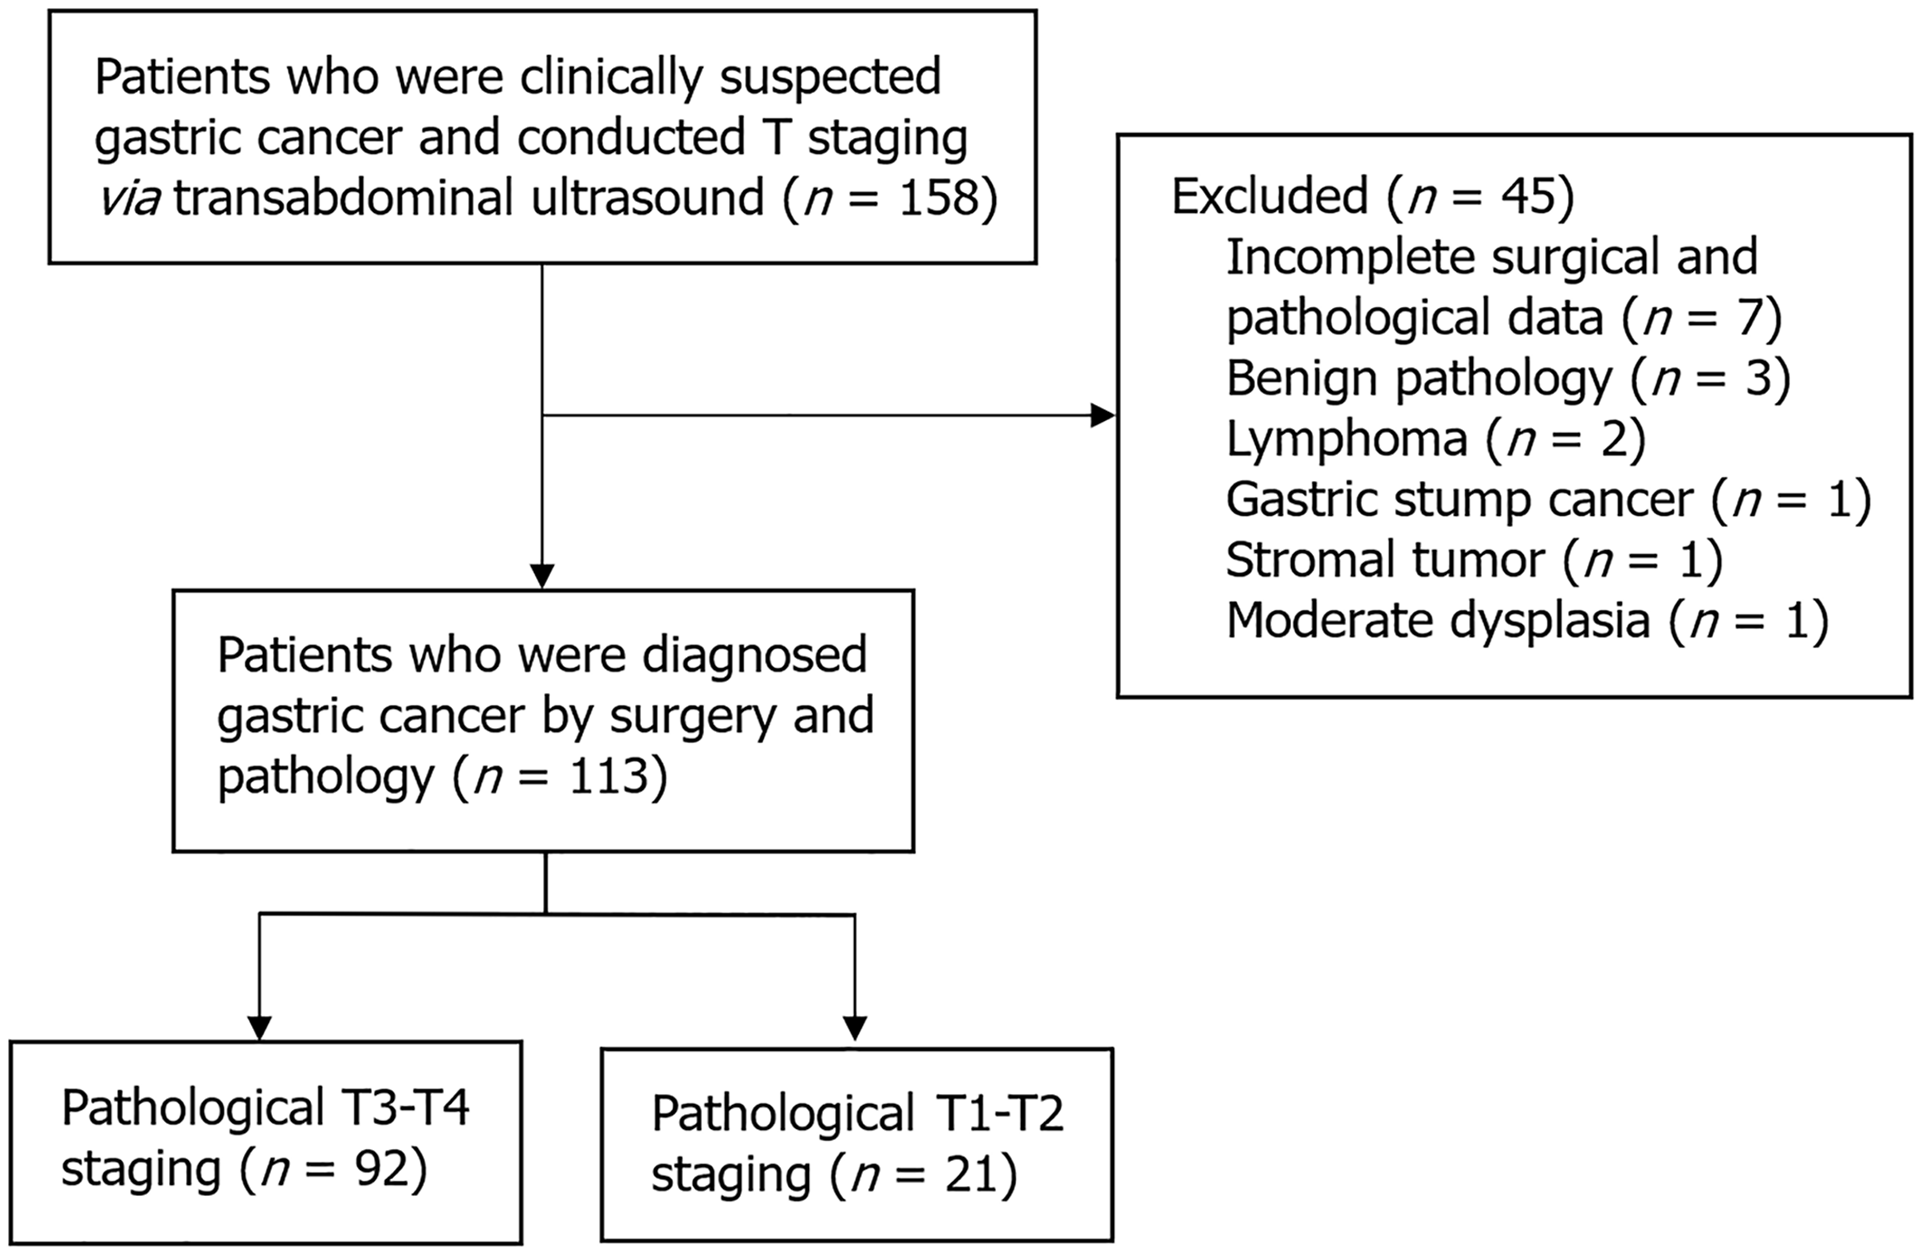

Figure 1 Flow chart of patient inclusion.